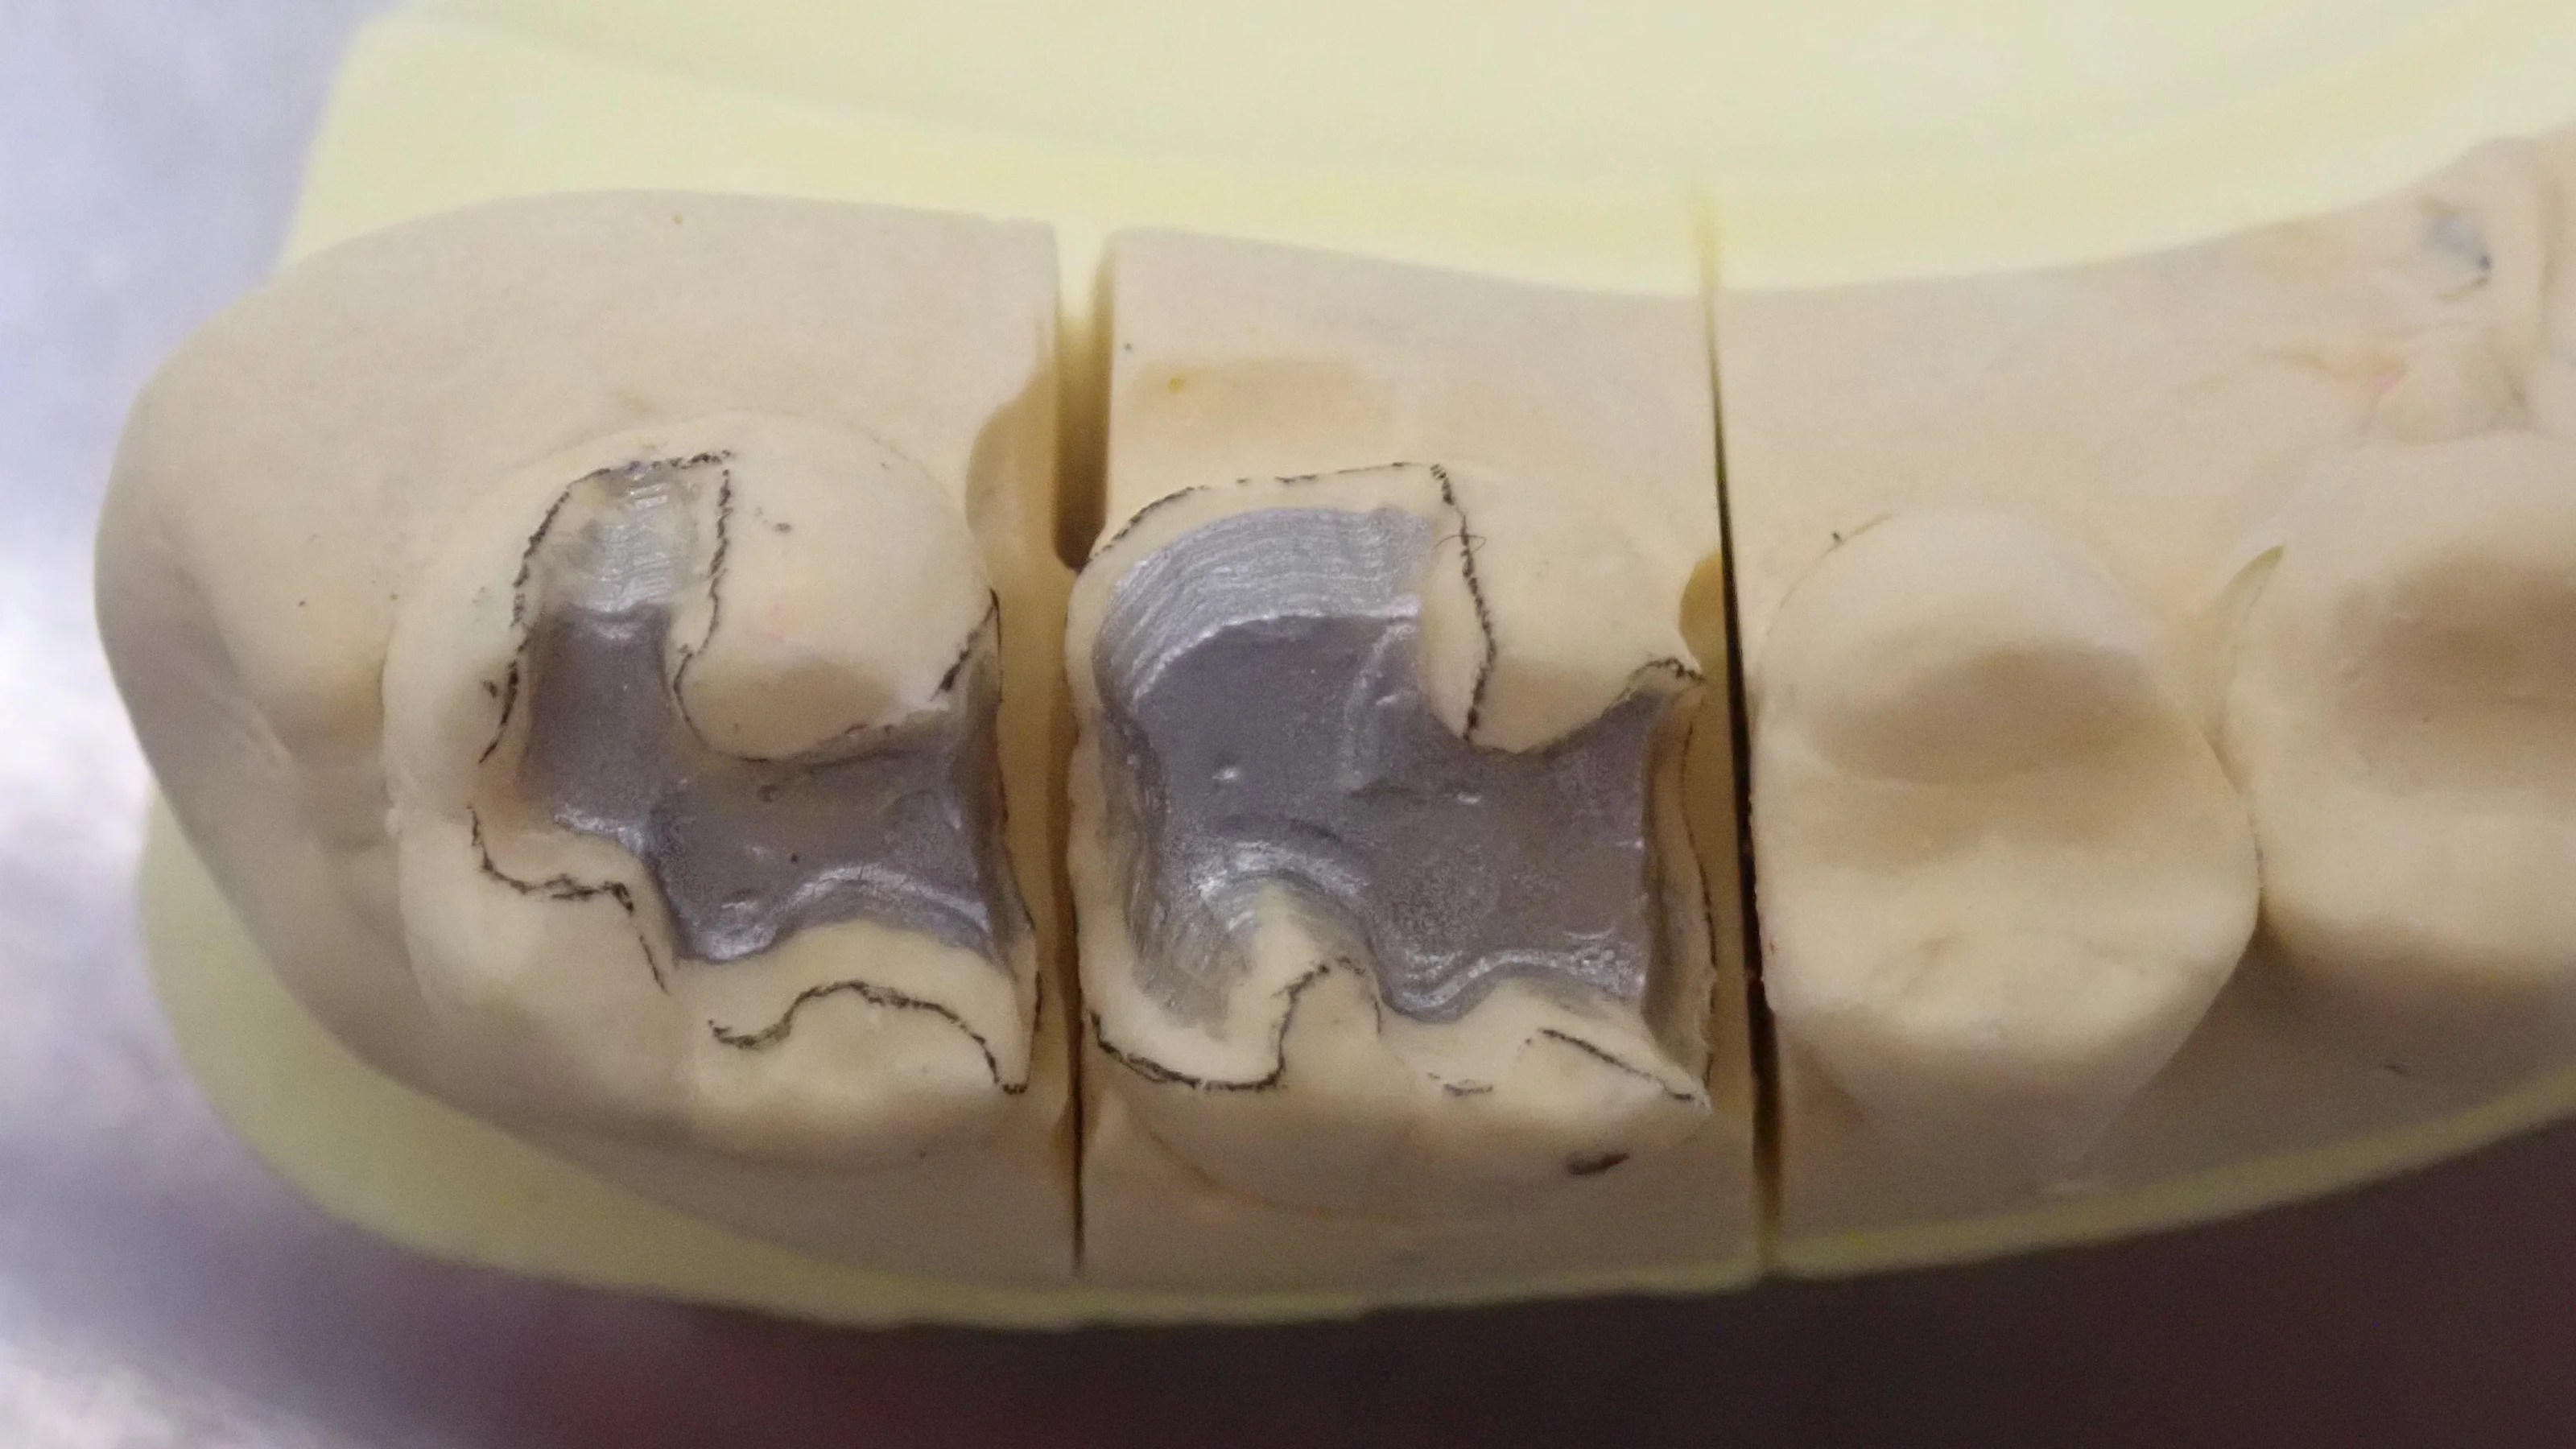

解剖学的知識を深め、更に治療精度を高めるために・・・

こんにちは。 まず最初に言っておきますが、今回の内容は一般の方向きでは全くありません。 どちらかというと歯科医師向けの内容になっているので、興味のある方のみ読んでみてください(笑) 最近様々なところで働かれている技工士さん方に出会う機会があ…

続きを読む →